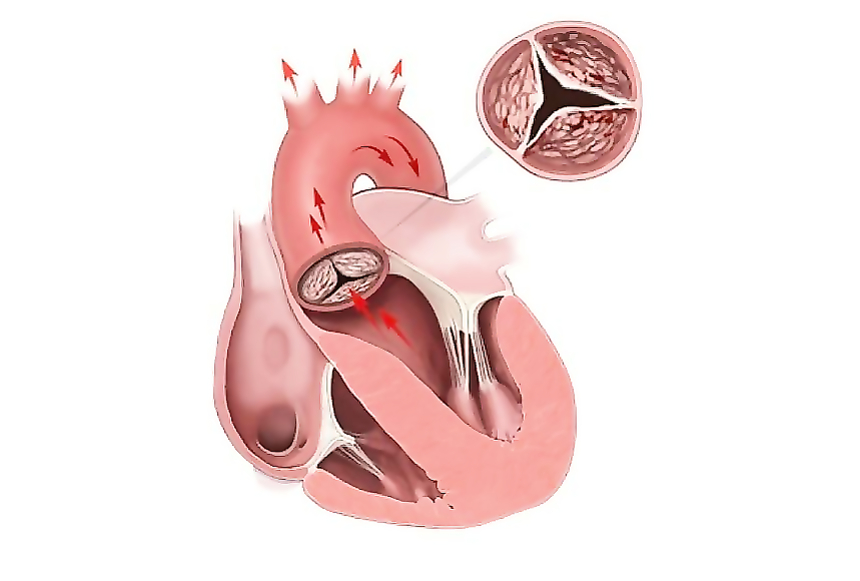

Фотографии и информация о приобретенных пороках сердца